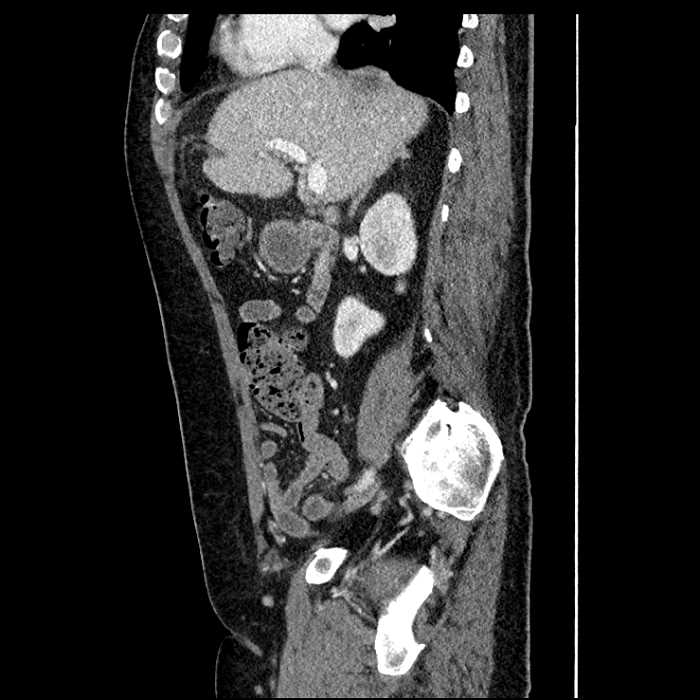

Age: 63

Sex: Male

Indication: Abdominal pain

• Large fluid density structure in hepatic segments 7 and 8 measuring 10 x 7 x 7 cm with internal septation and circumferential ill-defined low density compatible with edema

• Peripherally enhancing subcapsular collections along the anterior margin of the left hepatic lobe measuring 3 x 1 cm and 2 x 1 cm

• Clearly marginated fluid density structure in segment 7 and several other scattered tiny hypodensities, which likely represent cysts

Acute sigmoid diverticulitis complicated by a small contained perforation and a large abscess in the right hepatic lobe. Additional small subcapsular abscesses along the anterior margin of the left hepatic lobe.

Additionally, loss of the normal fat plane between the peridiverticular collection and adjacent thickened loops of small bowel raises the potential for an enterocolonic fistula.

• The classic CT imaging appearance is a double target sign with internal low density surrounded by an internal enhancing rim (capsule) and a low density external rim (edema)

Hepatic abscess showing the double target sign with low density internally surrounded by a thin inner enhancing rim (red arrow) and ill-defined outer low density rim (yellow arrow). Blue arrow indicates an internal septation. Red arrows: additional smaller subcapsular abscesses. Red arrow: focal contained perforation associated with diverticulitis.